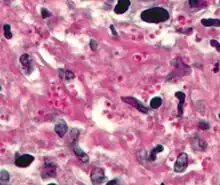

PAS diastase showing the fungus Histoplasma.

[13]Periodic acid-Schiff is a histology special stain used to mark carbohydrates (glycogen, glycoprotein, proteoglycans). PAS is commonly used on liver tissue where glycogen deposits are made which is done in efforts to distinguish different types of glycogen storage diseases. PAS is important because it can detect glycogen granules found in tumors of the ovaries and pancreas of the endocrine system, as well as in the bladder and kidneys of the renal system. Basement membranes can also show up in a PAS stain and can be important when diagnosing renal disease. Due to the high volume of carbohydrates within the cell wall of hyphae and yeast forms of fungi, the Periodic acid -Schiff stain can help locate these species inside tissue samples of the human body.